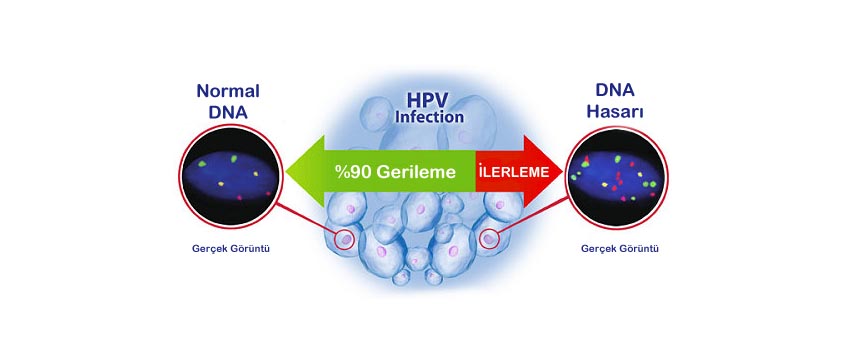

HPV DNA Test

The HPV DNA test is a medical screening used to detect the presence of high-risk types of Human Papillomavirus (HPV) that can lead to cervical cancer.